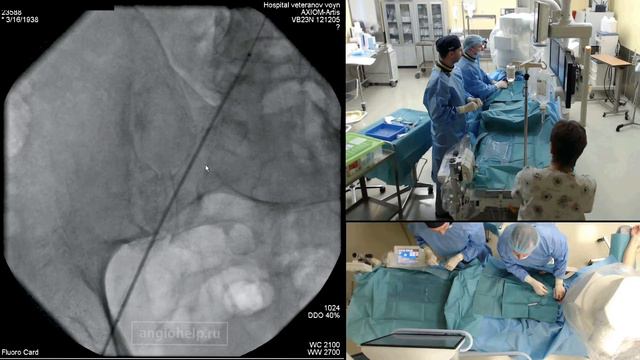

Баллонная ангиопластика и стентирование артерий нижних конечностей смотреть онлайн

Баллонная ангиопластика – это малоинвазивное внутрисосудистое (эндоваскулярное) вмешательство, при котором производится восстановление просвета сосуда, суженного атеросклеротической бляшкой. Процедура представляется собой введение через прокол сосуда специального катетера с баллоном на конце, раздуваясь в пораженной области баллон ликвидирует сосудистое сужение. После этого производится установка сетчатого стента, выполняющего роль внутреннего каркаса. Показаниями к операции является сужение просвета сосуда более чем на 60–70%, когда применение консервативной терапии показывает свою неэффективность. Наиболее часто баллонная ангиопластика применяется для восстановления просвета: - коронарных артерий, когда заболевание проявляется симптомами ишемической болезни сердца и стенокардии; - сонных артерий, атеросклероз которых вызывает ишемию различных отделов головного мозга; - крупных сосудов или периферических артерий нижних конечностей, когда заболевание сопровождается выраженным болевым синдромом в ногах, начиная от бедер и заканчивая ступнями. ------------------------------------------------- Медицинский центр «Мирт» — это платная частная клиника, предоставляющая пациентам лечебно-диагностические услуги более чем по 30 направлениям медицины в соответствии со всеми современными российскими и международными стандартами. - полный цикл лечения боли; - современный реабилитационный центр; - диагностика экспертного уровня - для иногородних пациентов трансфер и проживание. ✉ Связаться с нами: https://mirt-med.ru/patients/kak-s-nami-svyazatsya/ Многопрофильный медицинский центр Мирт https://mirt-med.ru/ Подробнее о центре https://youtu.be/vFadK7h3pJw Цель нашей работы – обеспечить доступную медицинскую помощь с использованием эффективных передовых, в том числе высокотехнологичных методик. Одним из ключевых направлений нашего медцентра является лечение болевых синдромов различного происхождения, в том числе связанных с дегенеративными заболеваниями позвоночника. В медицинском центре МИРТ проводятся высокотехнологические операции, диагностика и реабилитация по следующим основным направлениям: - нейрохирургия и вертебрология - урология - гинекология - травматология ортопедия - сердечно-сосудистая хирургия - общая хирургия и проктология - кардиология - дерматовенерология Мы в соц.сетях: https://vk.com/mc.mirt https://ok.ru/mc.mirt https://t.me/mirtmed ☎ 8 (800) 222-09-21 (бесплатно для жителей РФ)